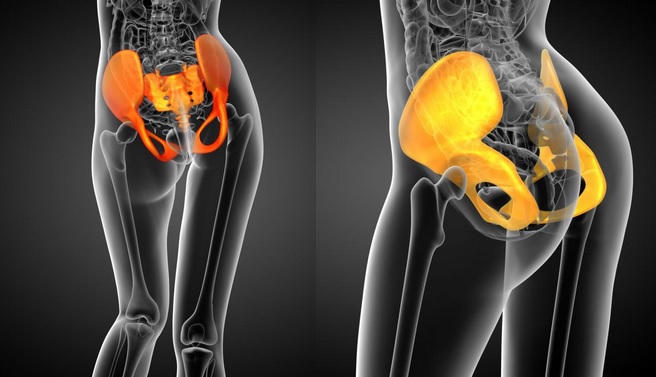

坐骨結節(ざこつけっせつ、Ischial tuberosity或いはTuber ischiadicum)は骨盤の下部にある左右に2つ突出した硬い骨の出っ張りで、人間が椅子や床に座るときに体重を支える重要な接地点です(Figure 1)。

坐骨結節は皮下脂肪・筋肉に覆われているため、脚を伸ばした状態で位置を確認するのは難しいです(Figure 2)。膝を曲げて尻を触るとすぐに分かります。左右の尻の下にゴリっとした硬い骨があり、指先で少し押すと硬くて丸い感触があります(Figure 3)。

上三角と下三角

骨盤の下部である骨盤底には、左右の坐骨結節と会陰部を横向きに結ぶ浅会陰横筋(Superficial Transverse Perineal Muscle)があります。女性の浅会陰横筋は男性より横に長く、坐骨結節の幅(坐骨結節間距離)が広いのが特徴です(Figure 6、Figure 7)。